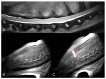

Kinematic MRI (kMRI) is a novel human imaging technique that couples the excellent soft tissue contrast and multiplanar capabilities of traditional MRI with kinematic potential. The study's goals are: (1) testing the feasibility of spinal cord and joints real-time kMRI; and (2) evaluating the quality of these kinematic studies as a new diagnostic option in veterinary medicine. Standard and real-time kinematic MRI were performed on cervical spine, elbow, and stifle joints of seven cadavers. Studies were repeated after a surgical insult aimed to create a certain degree of joint instability. A total of 56 MRI were performed-7 cervical spinal tracts, 3 elbow joints, and 4 stifle joints were examined. The technique was feasible in all the three regions examined. The images were considered of excellent quality for the stifle joint, good to fair for the cervical spine, whereas two of three elbow studies were considered to have unacceptable image quality. Additionally, real-time kMRI provided good to excellent information about stifle instability. Therefore we consider kMRI a promising technique in veterinary medicine. Further studies and an in vivo setting are needed to increase the quality of the kMRI images, and to fully evaluate clinical usefulness.